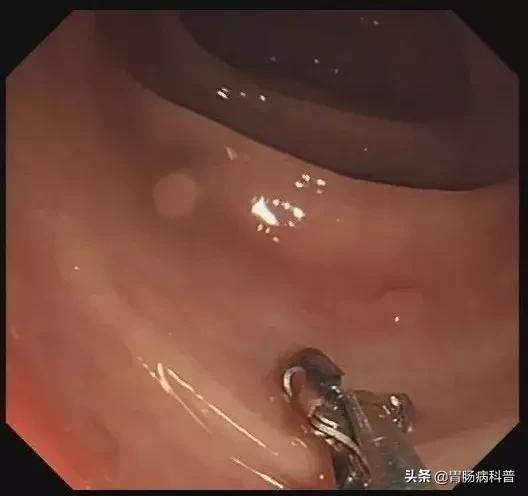

3.)如果蒂部较粗:可预先用尼龙绳或金属夹夹闭蒂部远端,再行电切术。